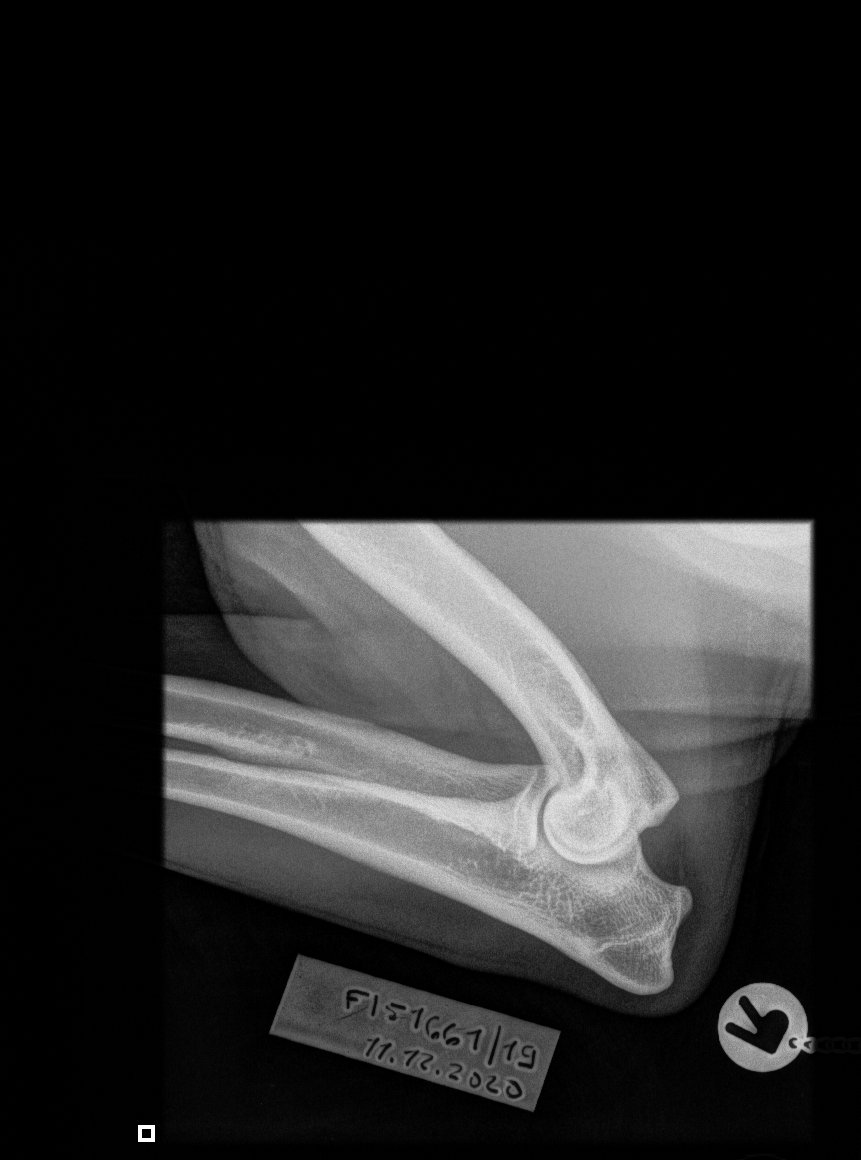

» HD A/A » ED 0/0 » silmät OK » Selkä LTV0 » Polvet 0/0